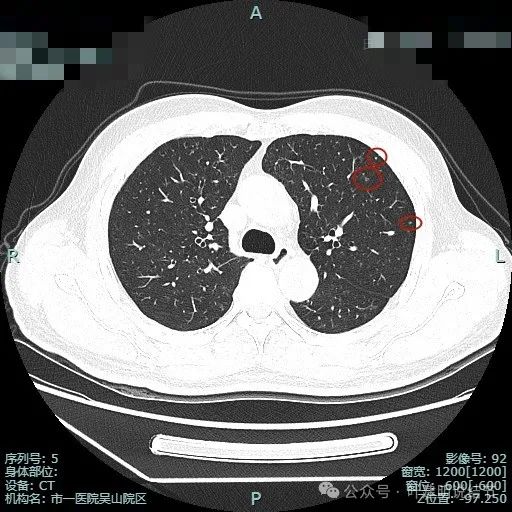

病灶3:右上叶点状偏高密度微小结节,只有1毫米许,无法定性,但增殖灶的可能性大点,因为密度感觉稍显高。

病灶4:左上叶点状高密度结节,良性可能性较大。

病灶7:左上叶胸膜下微小不足1毫米点状高密度,无法定性,但良性可能性大,因为密度显得较高;

病灶8:距离胸膜约1.5厘米许微小磨玻璃结节,大概1-2毫米之间,轮廓较清,以肺泡上皮增生可能性较大;

病灶9:左上叶胸膜下微小结节,密度不如病灶7高,又不如病灶8大,无法确定性质,但必能随访。

病灶10:右上叶胸膜下微小结节,表面不平,密度也非实性,显得形态不太规则,考虑良性或肿瘤范畴的原位癌或微浸润性腺癌均可能,但太小了,如果只有此灶只需随访。

病灶11:右肺实性结节,边缘略模糊,缺乏膨胀感,考虑良性可能性大些。

病灶12:右下叶微小结节,点状,密度较高,良性增殖灶可能性大。